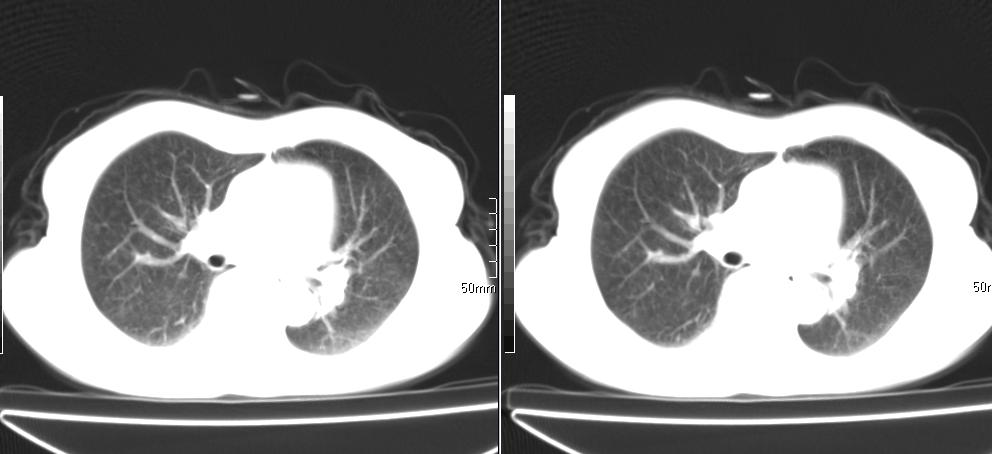

标题: CT26857:女,60岁,胃部不适前来就诊,不咳嗽,乏力,胸椎 [打印本页]

标题: CT26857:女,60岁,胃部不适前来就诊,不咳嗽,乏力,胸椎

1、胸椎有骨质破坏伴周软组织,考虑胸椎转移。2、考虑左肺上叶尖后段支气管开口区周围型肺癌可能。

1、胸椎有骨质破坏伴周软组织,考虑胸椎转移。2、考虑左肺上叶尖后段支气管开口区周围型肺癌可能。建议行纤支镜检查!

1、胸椎有骨质破坏伴周软组织,考虑胸椎转移。2、考虑左肺中央型肺癌可能。

支持中央型肺癌,胸椎转移。

1)考虑左肺中央型肺癌。2)胸椎转移瘤不排除;建议行mri检查。